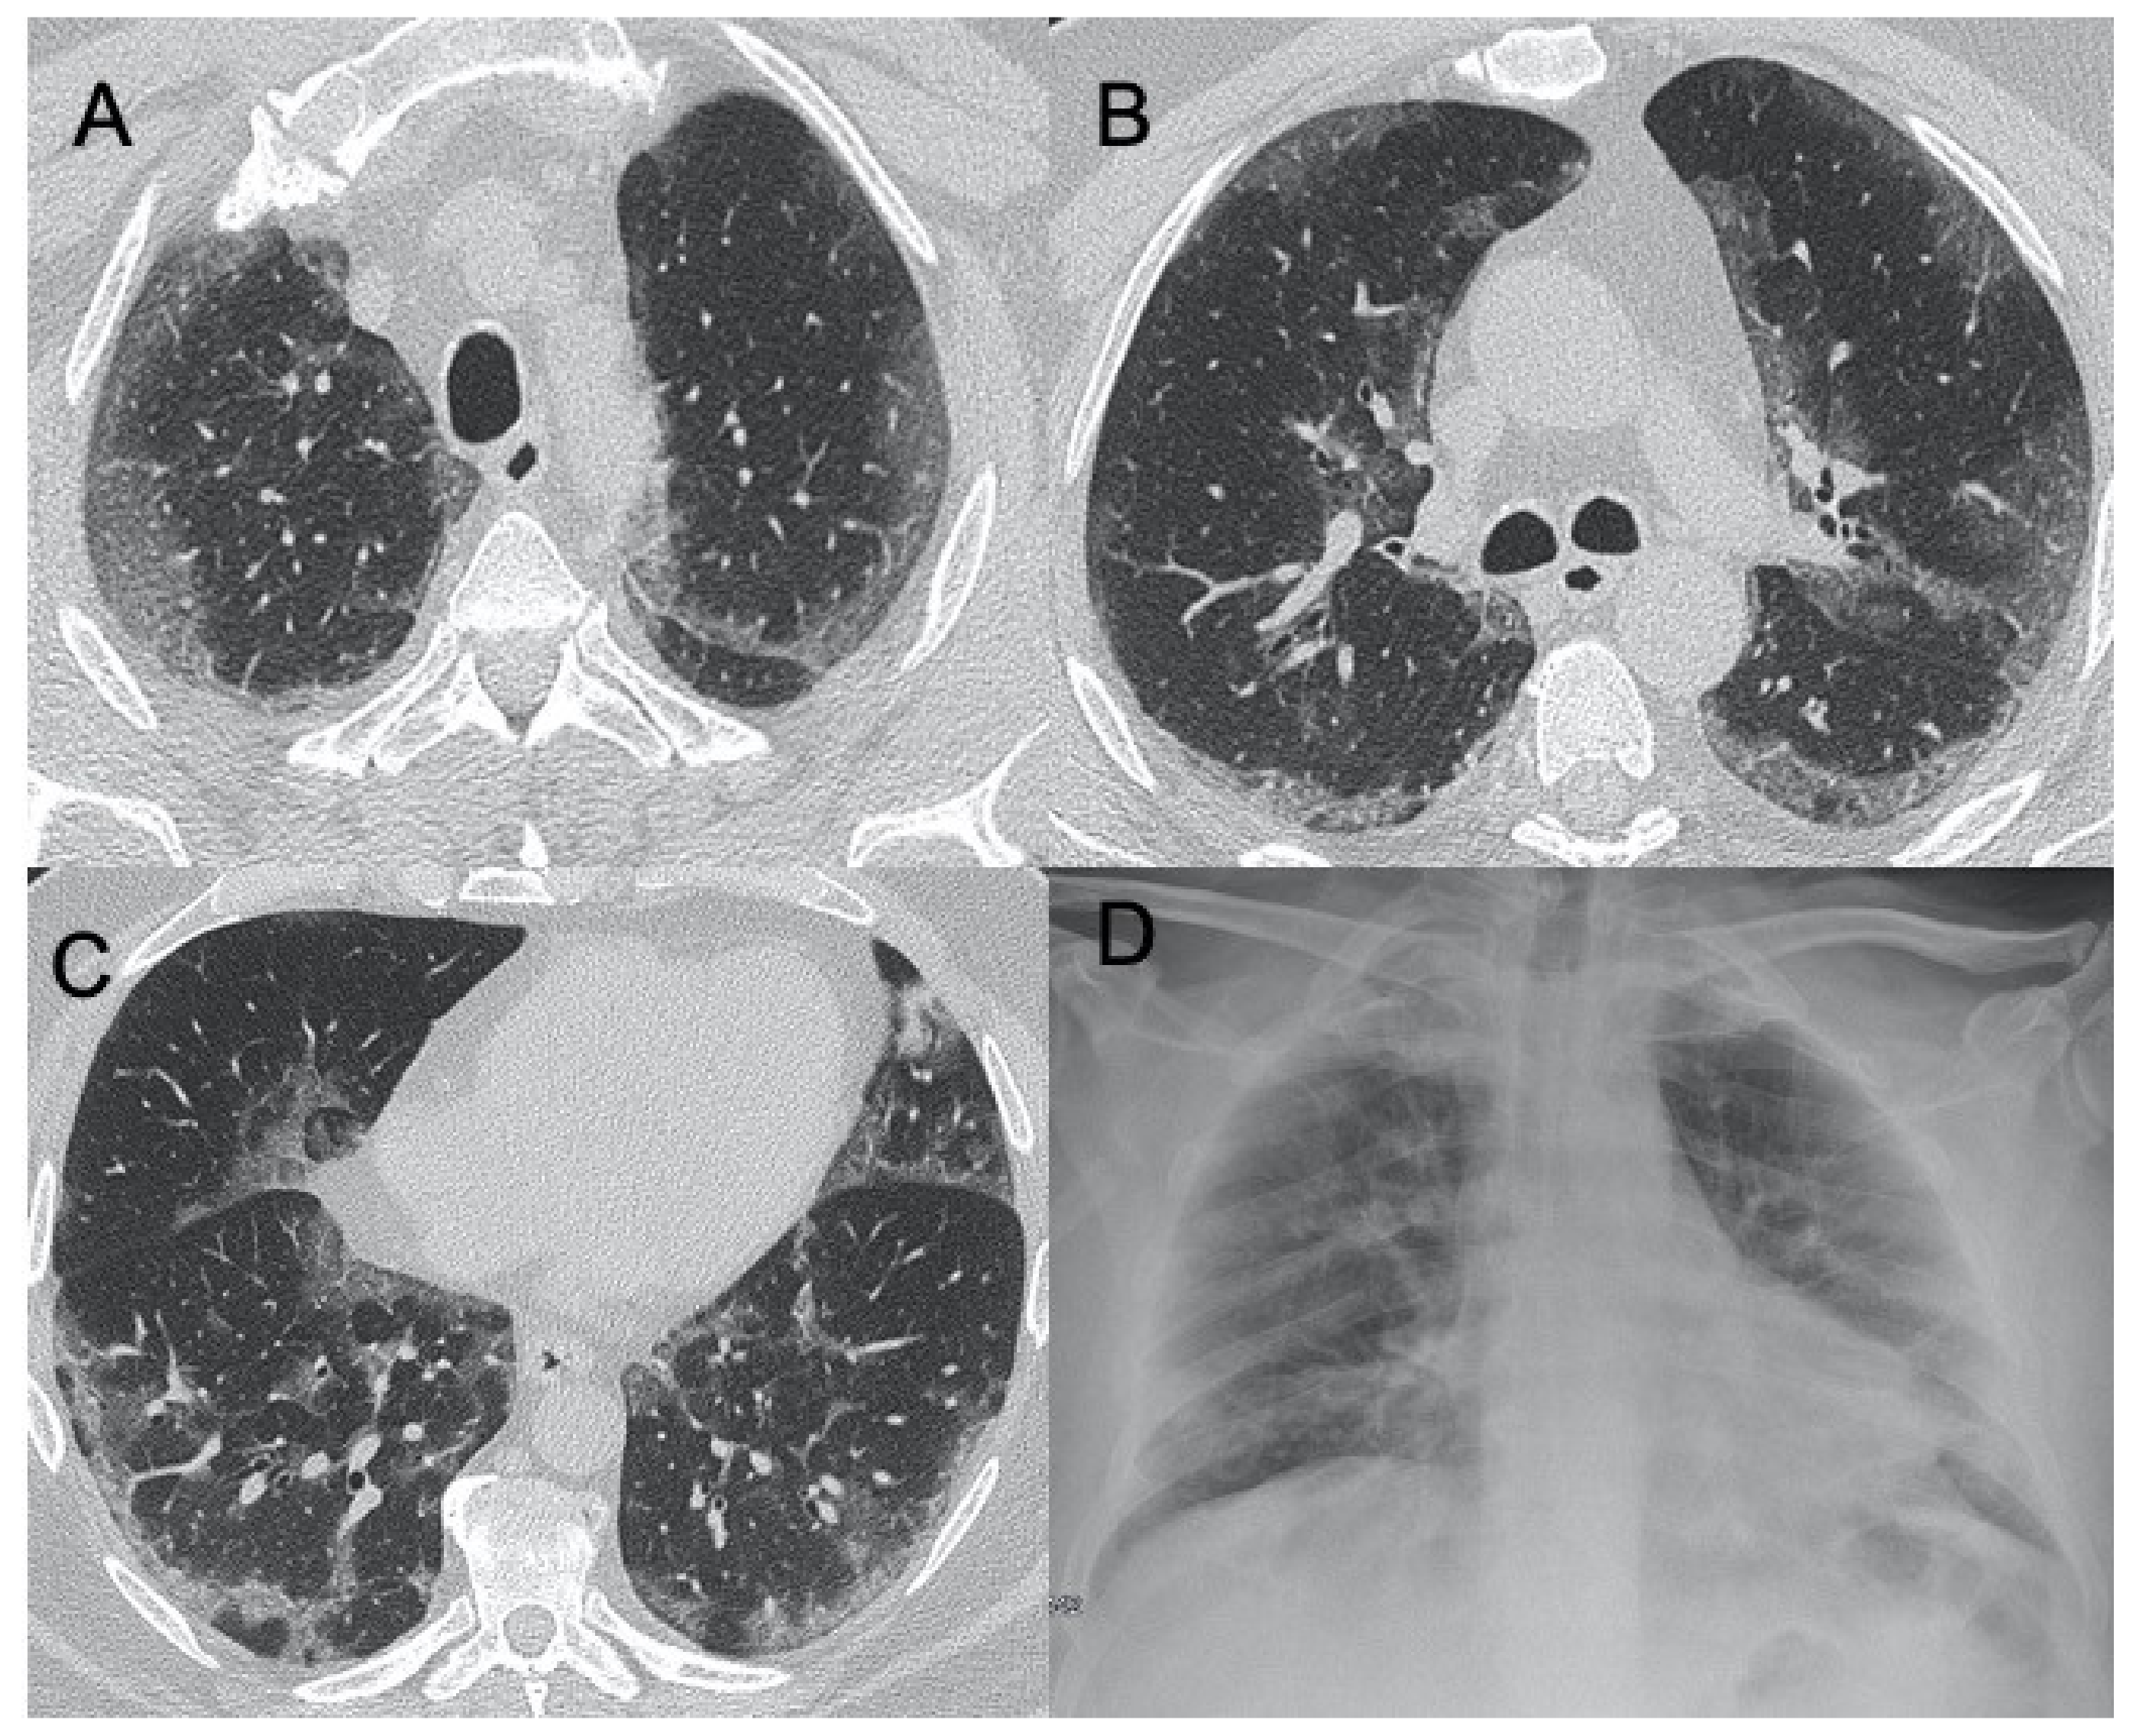

| Influenza A | Bilateral reticular-nodular opacities in association with areas of consolidation, usually in the lower lobes | Multifocal consolidations and diffuse areas of GGO. Lymphadenopathy, cavitation, pleural effusion, and pneumatocele were also observed | Figure 3 |

| H1N1 virus | Unilateral/bilateral GGO with or without associated areas of consolidation with predominantly peribroncho-vascular and subpleural distribution | Unilateral or bilateral GGO with or without associated areas of consolidation with predominantly peribroncho-vascular and subpleural distribution | Figure 4 |